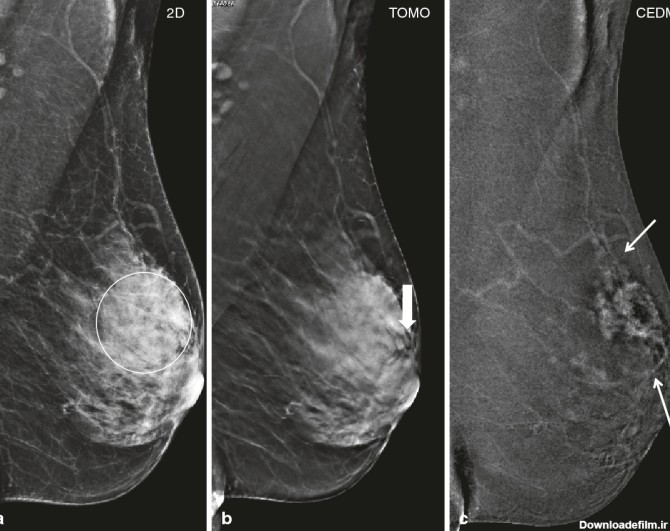

ماموگرافی هالوژیک یا ماموگرافی معمولی به این صورت می باشد که عکس گرفته شده از بیمار روی فیلم رادیولوژی ثبت می شود و مشابه همان عکس طی یک فرآیند به چاپ می رسد

ماموگرافی سه بعدی هالوژیک؛ماموگرافی سه بعدی در مرکز جردن به پزشکان کمک می کند تا از نظر سرطان سینه به طور کامل غربالگری کنند